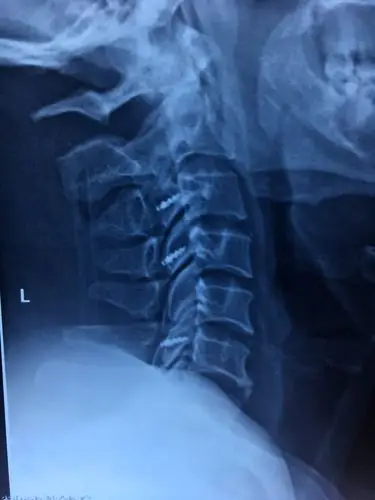

生活中你有见过这样的颈椎吗?你的亲人?朋友?或者是.陌生人?

溆浦县人民医院骨一科成功完成多例颈椎病的手术治疗!

颈椎后纵韧带骨化症

请帮我看一下我的颈椎有没有问题,脖子突然后仰的时候疼痛.

鹤岗鹤矿医院自行成功完成一例复杂陈旧性颈椎骨折脱位伴椎管狭窄

颈后路椎管扩大成形术治疗脊髓型颈椎病